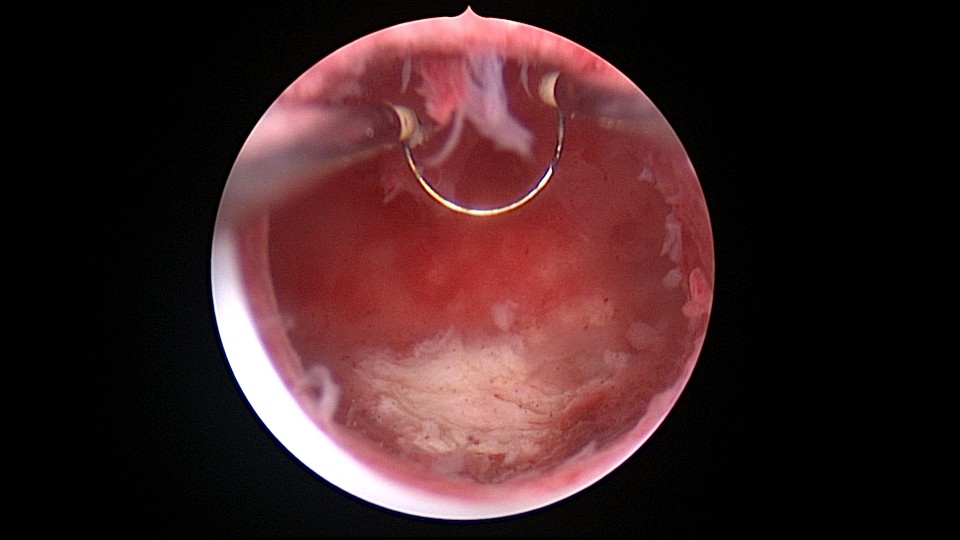

患者25岁,G1P0,停经52天,稽留流产,B超宫内偏右查见大小约2.4cmx1.0cmx1.7cm孕囊回声,形态规则,内可见直径约0.4cm的卵黄囊回声,未见胎芽,孕囊旁肌层最薄处厚约0.5cm,子宫中下段回声连续性欠佳,似可见一分隔回声。2021年7月宫腔镜探查,胚胎着床于宫腔前壁偏右,宫颈内口及宫腔左侧壁粘连。清除妊娠组织,单极电针分粘,恢复宫腔形态,双侧输卵管开口显露(第一次怀孕,宫腔粘连原因?)。2022年7月自然妊娠,2023年3月足月剖宫产分娩。2024年12月,外院人流术后1+月,宫内残留,与后壁肌层分界欠清,局部血流信号增多,到我院宫腔镜切除残留组织(后3张图片)。现患者30岁,G3P1。宫腔粘连常常不能阻止妊娠,但胚胎停育发生率增加。